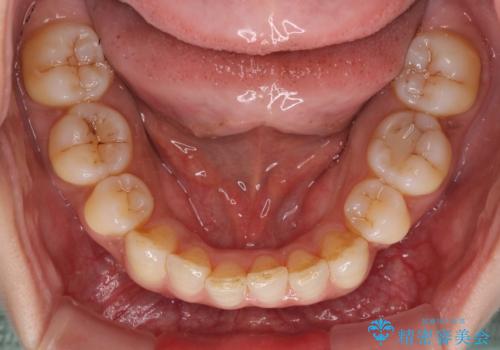

軽度な歯列不正 インビザライン・ライトによる矯正治療

- 上下前歯の叢生を気にして来院された患者様です。

費用を抑え、期間もあまりかけずに治療をしたいとのことで、インビザライン・ライトを用いて矯正治療を行うこととしました。

インビザライン・ライトは、製作できるアライナーの枚数に制限があるため、移動可能な量に限りがあります。

一方で、半年程度で治療を終えることができるため、軽度の歯列不正の患者様には大変お勧めです。